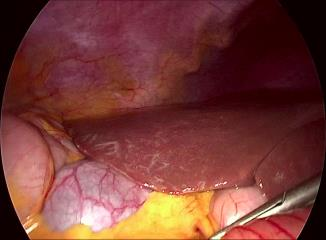

Visual question answering (VQA) in surgery is largely unexplored. Expert surgeons are scarce and are often overloaded with clinical and academic workloads. This overload often limits their time answering questionnaires from patients, medical students or junior residents related to surgical procedures. At times, students and junior residents also refrain from asking too many questions during classes to reduce disruption. While computer-aided simulators and recording of past surgical procedures have been made available for them to observe and improve their skills, they still hugely rely on medical experts to answer their questions. Having a Surgical-VQA system as a reliable 'second opinion' could act as a backup and ease the load on the medical experts in answering these questions. The lack of annotated medical data and the presence of domain-specific terms has limited the exploration of VQA for surgical procedures. In this work, we design a Surgical-VQA task that answers questionnaires on surgical procedures based on the surgical scene. Extending the MICCAI endoscopic vision challenge 2018 dataset and workflow recognition dataset further, we introduce two Surgical-VQA datasets with classification and sentence-based answers. To perform Surgical-VQA, we employ vision-text transformers models. We further introduce a residual MLP-based VisualBert encoder model that enforces interaction between visual and text tokens, improving performance in classification-based answering. Furthermore, we study the influence of the number of input image patches and temporal visual features on the model performance in both classification and sentence-based answering.